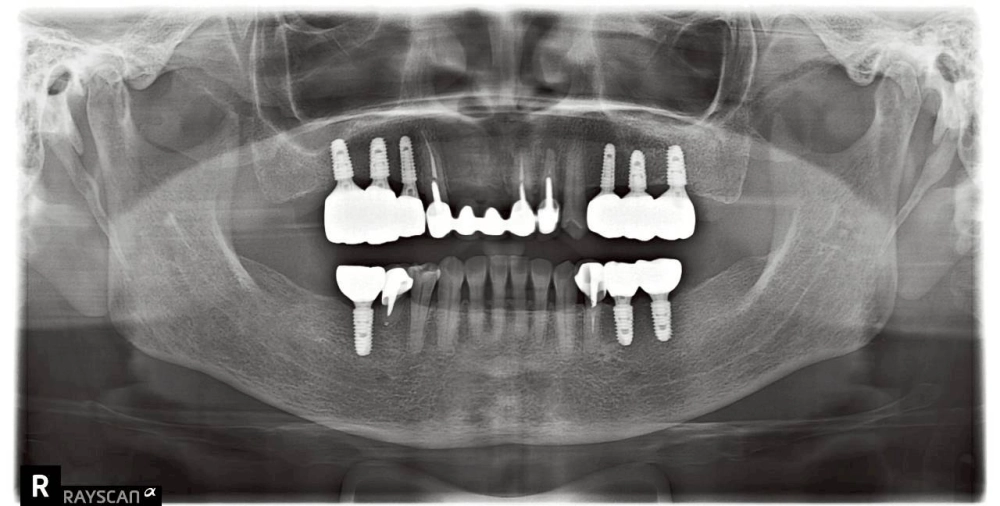

全口植牙重生紀實:找回咀疊的日常幸福

穩固基石的建立

• 力學回歸: 植體如基石般穩固,為全口提供對咬支撐。

術後回饋:重啟美味的人生下半場

現在的患者回診時笑容滿面。他分享道,終於能自信地夾起想吃的菜餚,不再擔心咬不動。

謝昂儒醫師的叮嚀

「牙齒的缺位,不該成為品味生活的阻礙。讓我們陪您,找回這份平凡的幸福。」